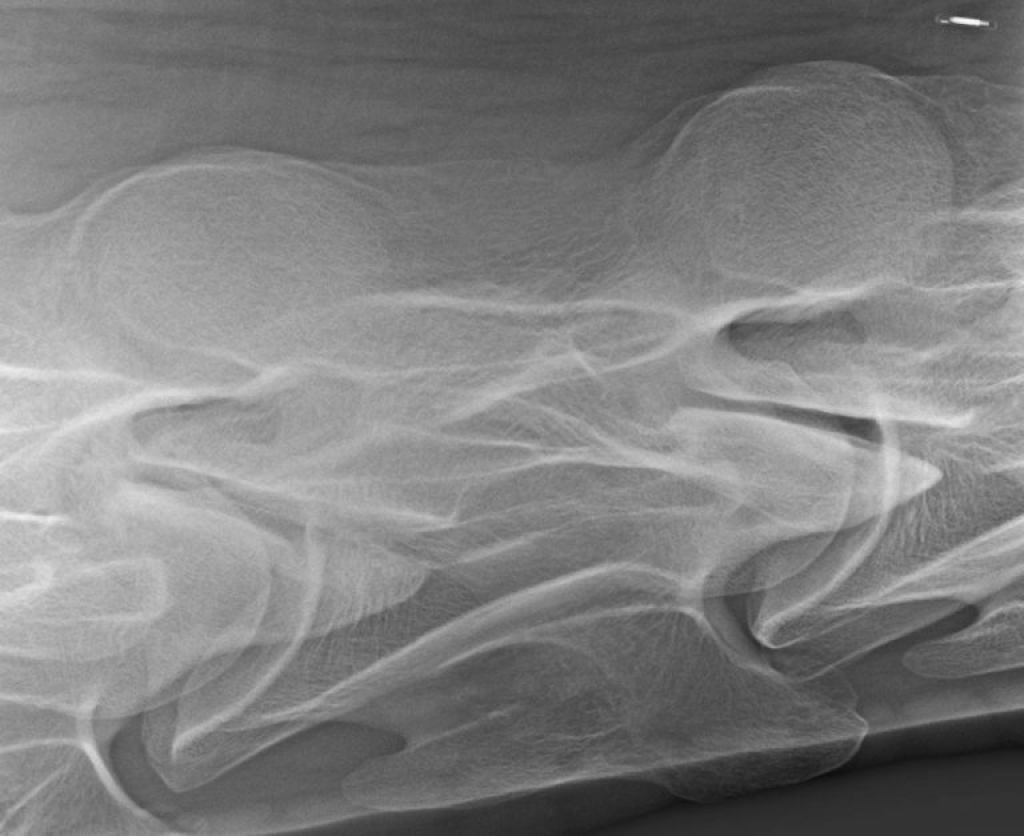

Het klinische onderzoek kunnen we aanvullen met beeldvorming. Op röntgenopnamen kunnen we de facetgewrichten van de gehele hals beoordelen, bij een zijdelingse opname zien we echter beide facetgewrichten over elkaar heen geprojecteerd. Om deze apart te kunnen beoordelen kunnen we “schuine” foto’s maken, ofwel uitprojecties.

Links: Wervellichamen T1-C6

Rechts: Rontgenopnamen T1-C7

Wervellichamen T1-C6

Rontgenopnamen T1-C7

Links: Facetgewricht röntgen

Rechts: Uitprojectie facetgewricht

Facetgewricht röntgen

Uitprojectie facetgewricht